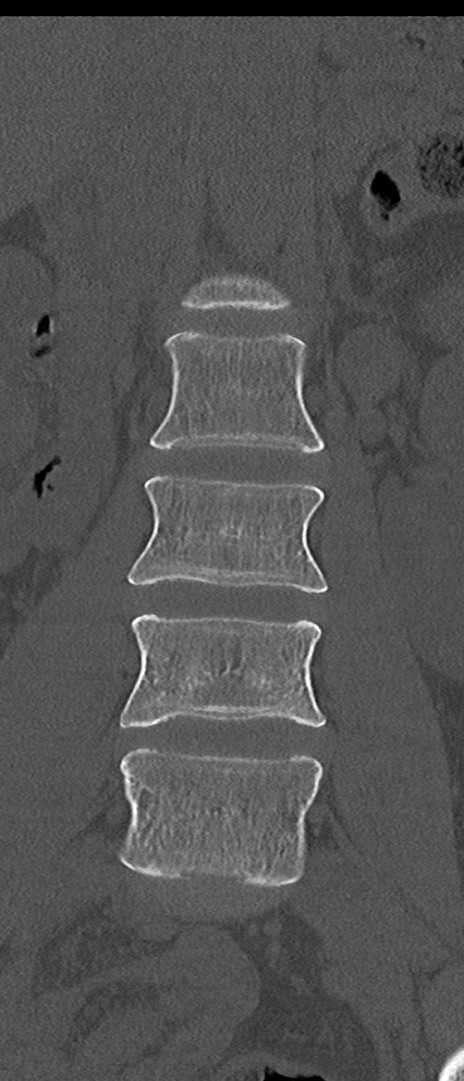

【整形】TIPS症例4 腰椎CT(冠状断像)

腰椎CT